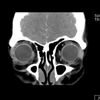

@heyirmajj: Day 1 of tepezza infusion for my Graves’ disease 🦠❤️ #gravesdisease #chronicillnessawareness #thyroid

I start my Tepezzo journey soon! My eyes look like yours with one bulging. Hoping this helps! Good luck and thank you for sharing! ♥️